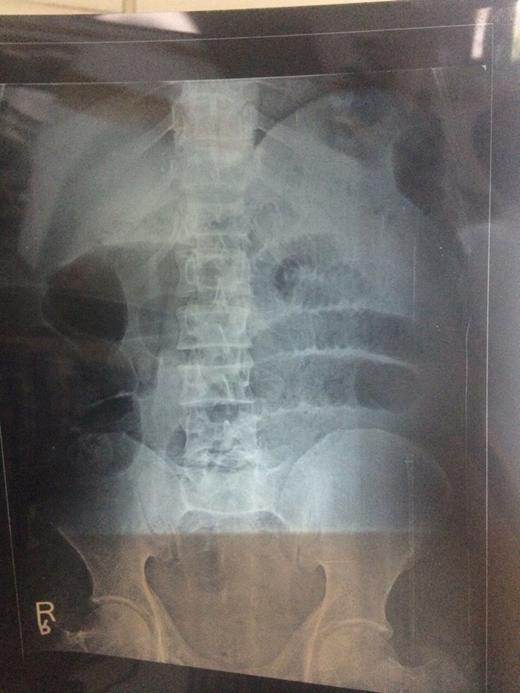

A 51-year-old male was brought in our casuality in shock with history of abdomen pain and non-passage of flatus and stools for 24 h. His blood pressure was 78/56 mmHg and pulse rate was 112 min−1. Abdomen was distended and tender. He was resuscitated, and X-ray of abdomen revealed multiple dilated gut loops as depicted in Fig. 1. Per rectal examination revealed soft faecal matter. Ultrasonography showed multiple dilated gut loops with minimal intergut fluid. CT was not available. Urgent exploratory laparotomy was done. Ileum was wrapped around sigmoid colon making two complete turns with gangrene of sigmoid colon and ileum as depicted in Fig. 2. Clamps applied on large gut and sigmoid colon removed followed by ileum, and end jejunostomy was done in view of haemodynamic unstability of the patient along with descending sigmoid colon anastomosis. The patient expired after 2 weeks despite exhaustive efforts due to complications of short bowl syndrome.